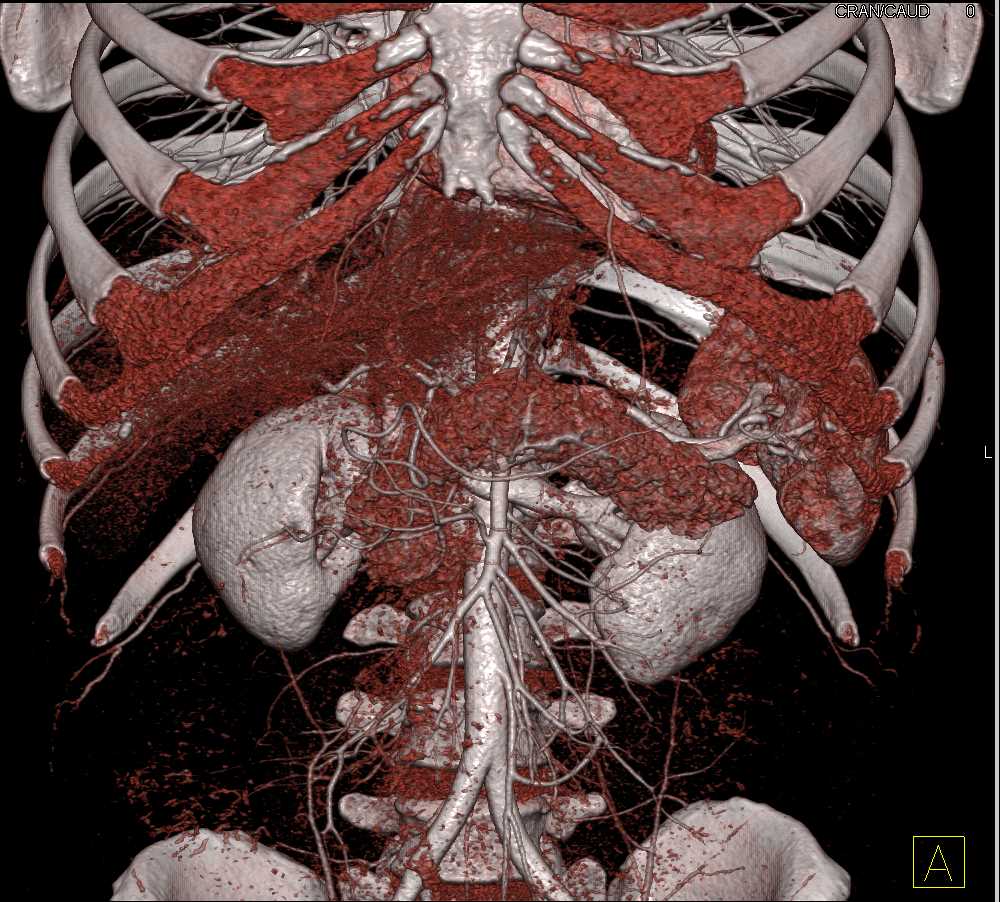

Neuroendocrine Tumor Body of Pancreas